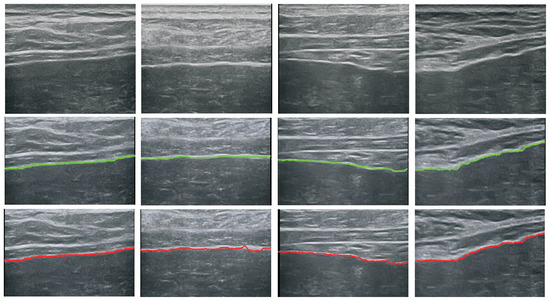

5.1. Performance of the Detector